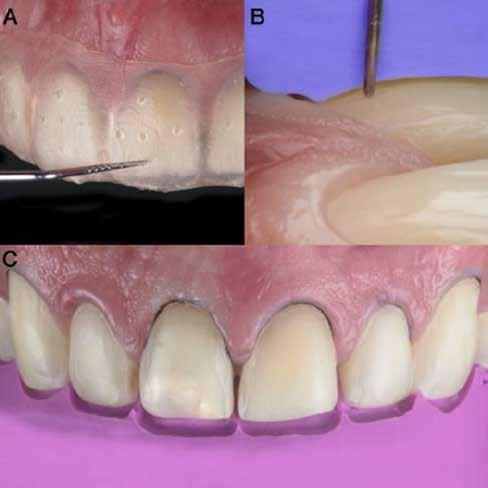

Az előzetes állapotfelmérést és a kezelés megtervezését követően a fogakat minimál invazív módon preparáltuk (1. a-b ábrák), majd az előkészített fogak ínybarázdáiba fonalbehelyező eszköz segítségével (113 Serrated Gingival Cord Packer, Hu-Friedy, Chicago, Illinois) teflonszalagot helyeztünk (Loctite Thread Seal Tape, Henkel Loctite Corp., Egyesült Államok), (1. c ábra). A hagyományos retrakciós fonalak helyett, a rugalmasságuk miatt előnyösebbnek tartjuk a teflonszalagok használatát. A kofferdámot (Dental Dam, Nic Tone, Bukarest, Románia) az előkészített fogakon kívül, az azoktól disztálisan elhelyezkedő egy-egy fognak megfelelően is perforáltuk.

Mivel a felső fogív első kisőrlőfogtól ellenoldali első kisőrlőfogig terjedő részét terveztük kerámia héjak segítségével ellátni (14-24), ezért az izolálást ugyanezen fogív második kisőrlőfogtól második kisőrlőfogig terjedő részére (15-25) helyeztük fel (2. a ábra). A kofferdám rögzítését a második kisőrlőfogakra helyezett kapcsok segítségével (Rubber Dam Clamps #2, Hu-Friedy, Chicago, Illinois, Egyesült Államok) biztosítottuk (2. b ábra). Ezt követően a gumilepedő fogakat körülvevő szélét kézi fonalbehelyező eszközzel és finom levegőáramlattal az ínybarázdákba forgattuk. A folyamat a következőképpen zajlott: a kézi eszközzel a kofferdámot a fognyaknak megfelelően finoman a szulkusz irányába fordítjuk, majd az eszköz végét a fognyaknak megfelelően vezetjük, miközben a lepedőt a puszterből jövő levegő segítsé-

A gumilepedő és a kiválasztott kapcsok (A). A kisőrlőfogakra helyezett kapcsok stabilizálják a kofferdámot (B). A gumilepedő ínybarázdákba történő beforgatása fonalbehelyező eszköz és levegőáramlat segítségével (C). Közvetlenül a héjak felhelyezése előtt a frontfogakra helyezett kapcsok (D).

ábra: A kapcsok eltávolítása és a kismetszőfogakra készült héjak beragasztása. A kapcsok nagymetszőfogakról történő eltávolítása (A). A kapcsok eltávolítása után látható állapot (B). A nagymetszőfogak és a szemfogak teflonszalaggal történő izolálása (C). A kismetszőfogak ínykapcsokkal történő kiegészítő izolálása (D). A héjak átadása után látható állapot (E).

gével finoman az ínybarázdába fordítjuk (2. c ábra). Azokra a fogakra, amelyekre aktuálisan héjakat akartunk helyezni, ezen felül kiegészítő kapcsokat is helyeztünk (Hygenic Brinker Clamp #B4, Coltene/Whaledent Inc., Cuyahoga Falls, Ohio, Egyesült Államok), (2. d ábra) Ebben a stádiumban érdemes a héjakat még bármilyen ragasztóanyag vagy próbapaszta nélkül a helyükre illeszteni (dry tryin). Erre azért volt szükség, hogy még a tényleges ragasztási folyamat megkezdése előtt ellenőrizni tudjuk a restaurátum és a fog pontos illeszkedését, valamint a széli záródási vonalhoz való akadálytalan hozzáférést (3. a ábra). Ideális esetben a héjak felhelyezését párosával, a középvonaltól disztál felé haladva végezzük. Ennek megfelelően a jobb (1.1) és bal felső nagymetszőfogakra (2.1) kapcsokat helyeztünk, majd a szomszédos fogakat teflonszalag segítségével izoláltuk. Ezt követően az 1.1-es és 2.1-es fogak héjak elhorgonyzására szolgáló felszíneit 32%os foszforsavval (Uni-Etch w/BAC, Bisco Dental, Schaumburg, Illinois, Egyesült Államok) 30 másodpercen keresztül kondicionáltuk. Ez után a felszínek vízzel történő lemosása és óvatosan

leszárítása következett (3. b ábra). A fogfelszínek előkészítésének utolsó lépéseként a primert és az adhezívet (OptiBond FL, Kerr Dental Orange, Kalifornia, Egyesült Államok) a gyártói javaslatnak megfelelően a felszínekre applikáltuk, majd 20 másodpercen keresztül polimerizációs lámpával világítottuk (Valo LED Curing Light, Ultradent Products Inc., South Jordan, Utah). Az 1.1-es és 2.1-es fogakat borító héjak ragasztása során világos színű, fényre kötő ragasztócementet (Variolink Esthetic LC, Ivoclar Vivadent, Schaan, Liechtenstein) alkalmaztunk. A ragasztóanyagot először a héjak belső felszínére vittük fel, majd ezeket az előkészített fogfelszínekre helyeztük (3. c ábra). Az approximális felszíneken megjelenő cementfelesleget egy ecset (Profi Natural Bristle Brush, Renfert, Hilzingen, Németország) és fogselyem (Oral-B Glide Pro-Health Deep Clean Floss, Procter & Gamble, Cincinnati, Ohio, Egyesült Államok) segítségével még a ragasztóanyag megvilágítása előtt eltávolítottuk. A megvilágítás során a különböző fogfelszíneket (labiális, meziális, disztális és incizális) 20-20 másodpercen keresztül világítottuk meg (3. d ábra)

Ezt követően a felső nagymetszőkre helyezett kapcsokat

5. ábra: A cementfelesleg eltávolítása. A cementfelesleg fognyakról történő eltávolítása (A). A cementfelesleg approximális területekről történő eltávolítása (B). A cementfelesleg penge használatával történő eltávolítása (C).

egy kapocsfeszítő (4 Rubber Dam Clamp Forceps, Hu-Friedy, Chicago, Illinois, Egyesült Államok) segítségével eltávolítottuk (4. a-b ábrák). Ezután a kismetszőfogak előkészítése következett. Még a kapcsok felhelyezése előtt a szomszédos fogakat, azaz a jobb és bal felső szemfogat, valamint a felső nagymetszőfogakat (1.3, 1.1, 2.1, 2.3) teflonszalaggal izoláltuk (4.c. ábra). Ezután a korábban részletezett ragasztási protokollt követve a kismetszőfogakra készített héjakat beragasztottuk. Ezt a folyamatot a felső szemfogak, és végül az első kisőrlőfogak esetében is megismételtük (4. d-e. ábrák)